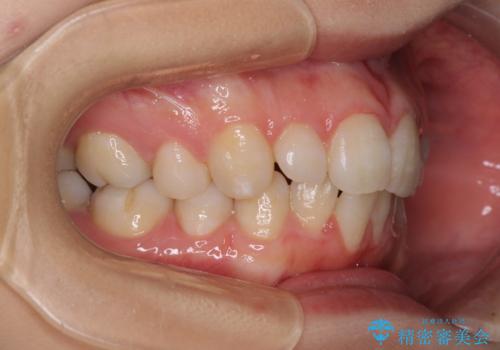

- 30代女性

- 下顎前歯を中心に、以前行った矯正治療の後戻りが気になるとのことで来院された患者様です。

後戻りは軽度であったため、インビザライン・ライトにて治療を行うこととしました。